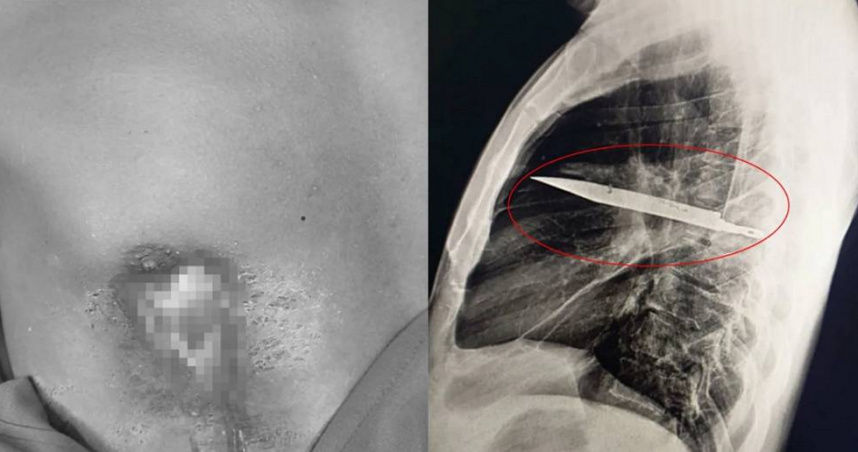

東非坦尚尼亞一名44歲男子右邊乳頭流膿,就醫才發現胸腔內有一把刀子,在體內長達至少8年時間。(圖/翻攝自X/Journal of Surgical Case Reports)

經醫師詳細問診,才知道男病患近10年內在一次次暴力衝突中,臉部、胸部、背部和腹部都有遭到利器割傷,當時有接受治療,之後生活也很正常,直到前段時間才發生右邊乳頭流膿的情形。醫師立刻替男病患安排胸腔X光檢查,驚見他的胸腔內插著一把小刀,奇妙的是,這把刀從他的右肩胛骨刺入,避開所有重要器官。